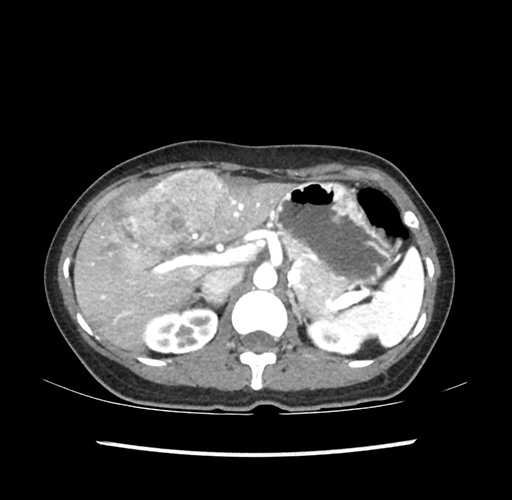

Imaging Analysis

Look through the patient's CT scan to identify any areas of concern for the necessary procedure.

Based on your CT findings, which issue(s) would give reason for "planned slowing down moment(s)" in this case?